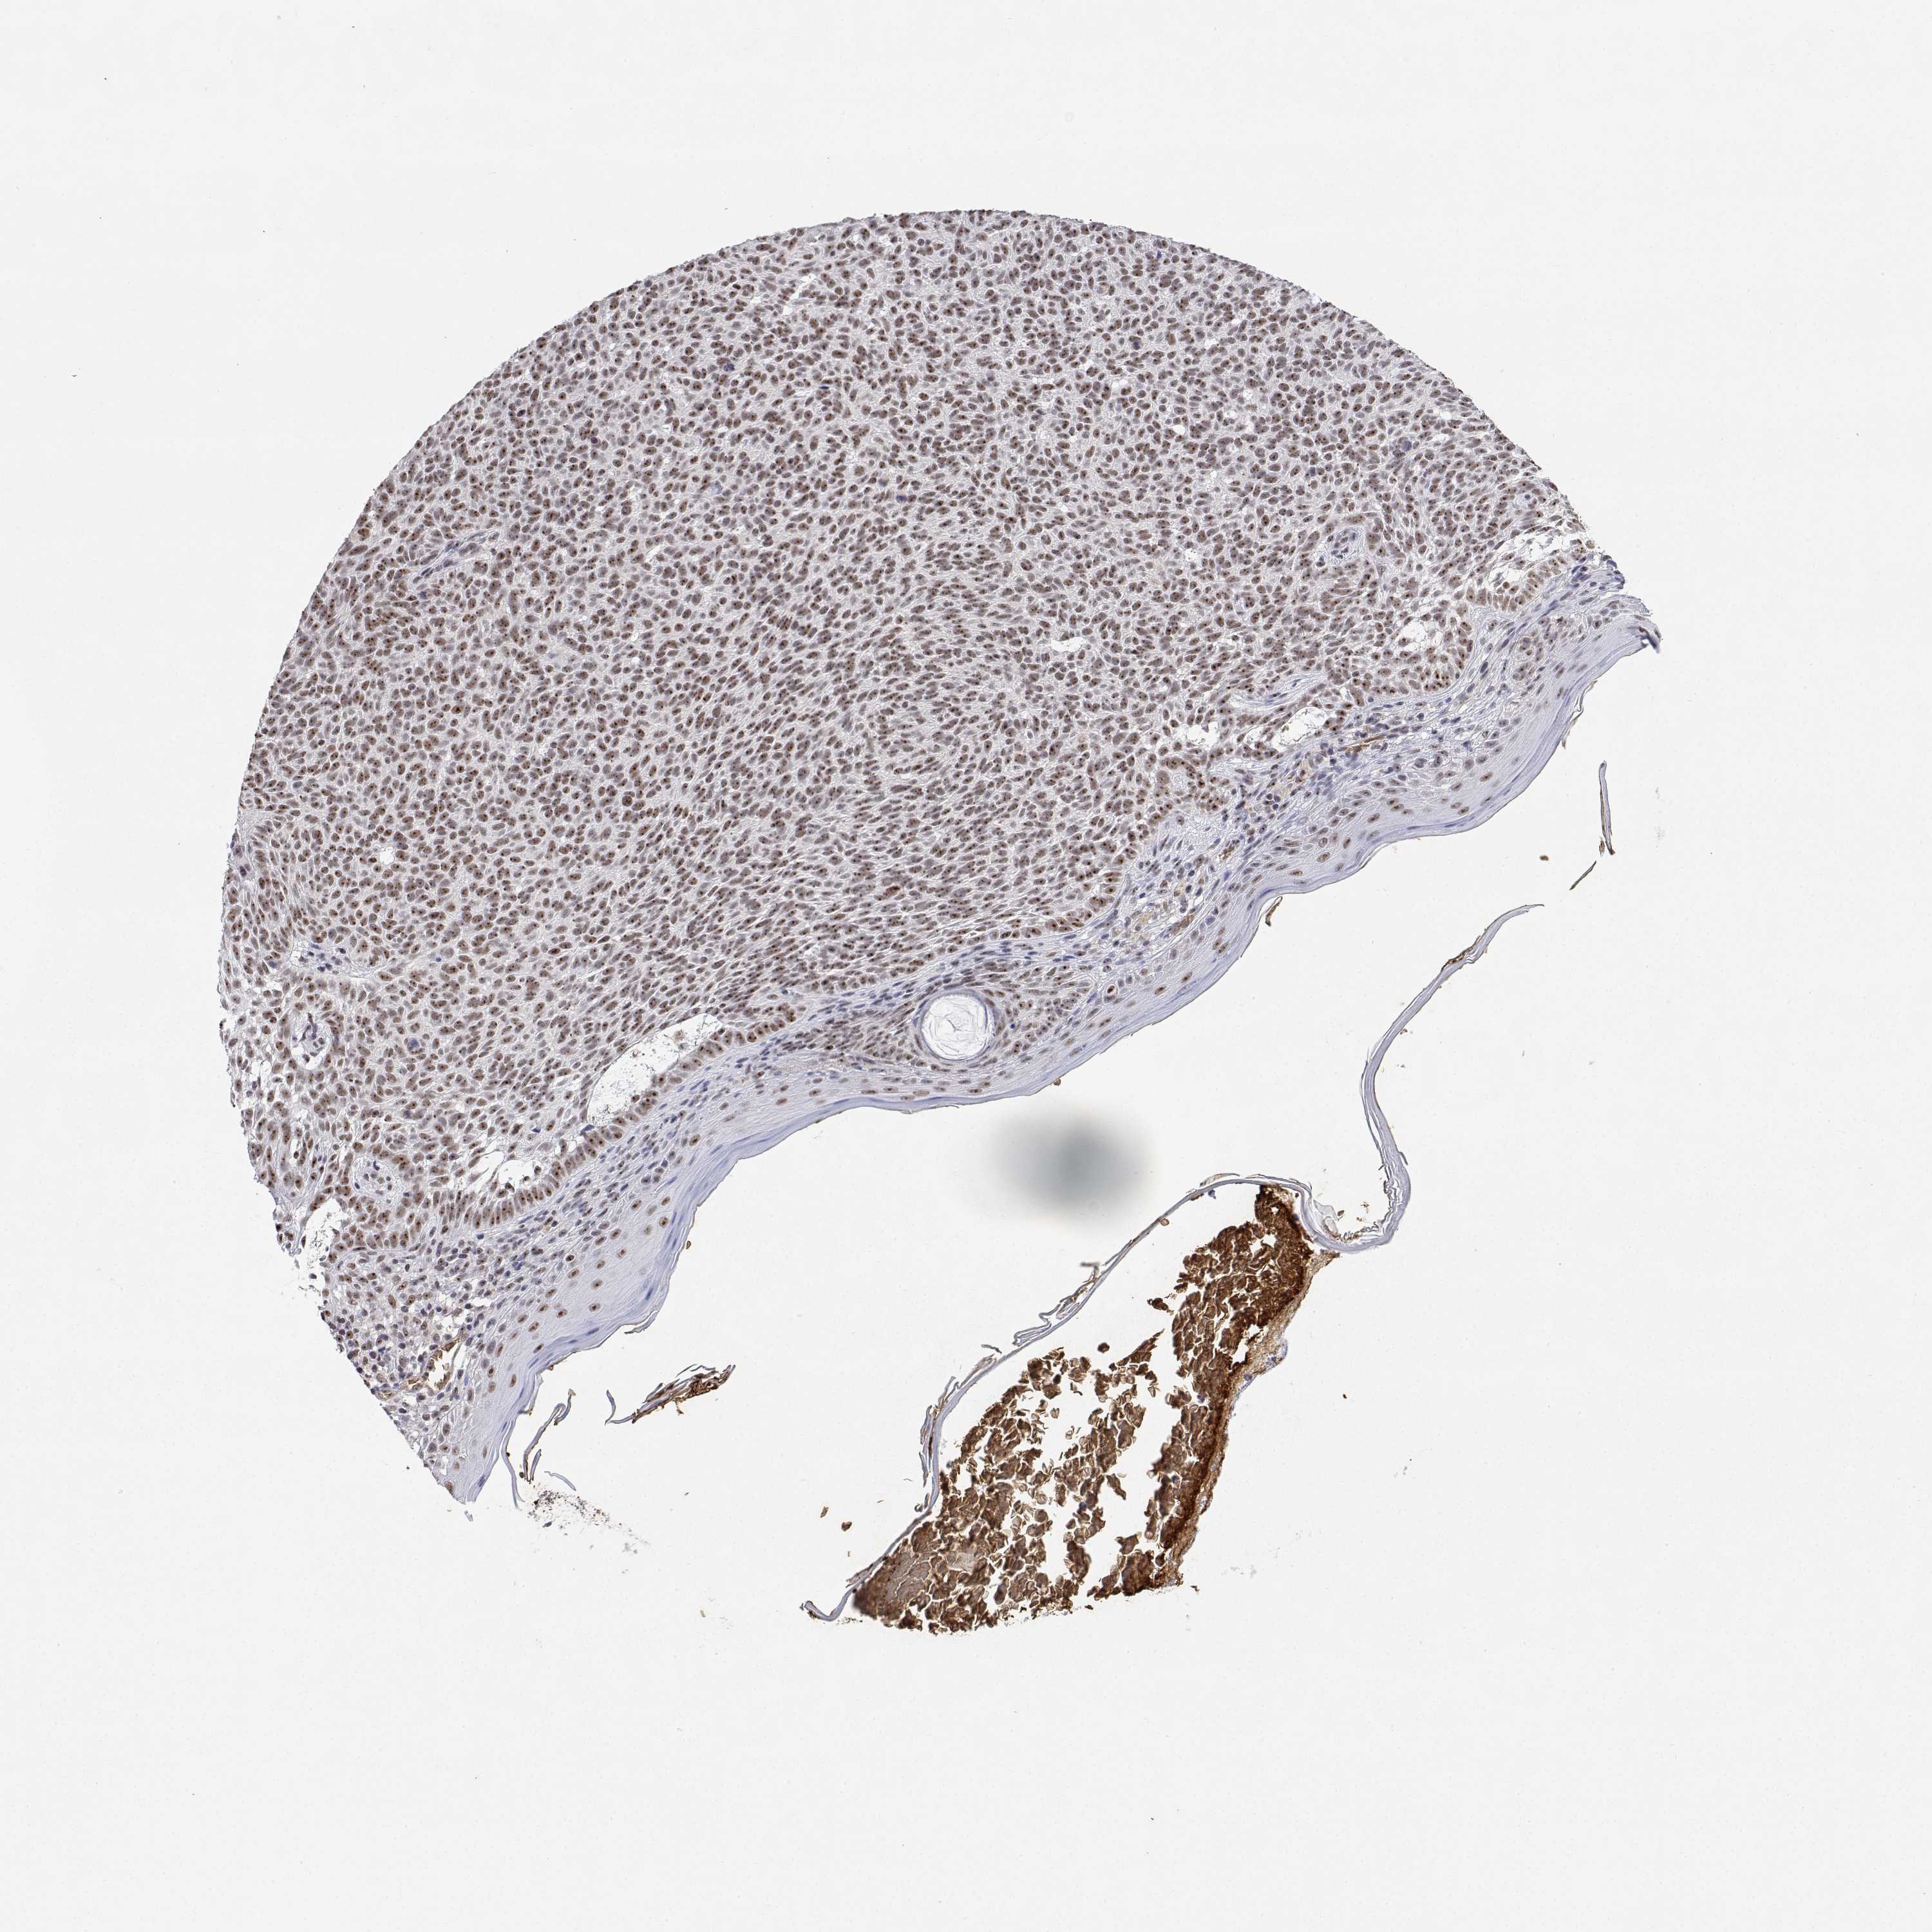

SKIN CANCER - Protein expressioni

A mouse-over function shows sample information and annotation data. Click on an image to view it in a full screen mode. Samples can be filtered based on level of antibody staining by selecting one or several of the following categories: high, medium, low and not detected. The assay and annotation is described here.

Each image is clickable and will lead to virtual microscopy that enables deeper exploration of all samples and also displays staining intensity scores, fraction scores and subcellular localization as well as patient and tissue information for each sample.

Antibody HPA003890

Staining

High

Medium

Low

Not detected

Intensity

Strong

Moderate

Weak

Negative

Quantity

>75%

75%-25%

<25%

None

Location

Nuclear

Cytoplasmic/membranous

Cytoplasmic/membranous,nuclear

Basal cell carcinoma